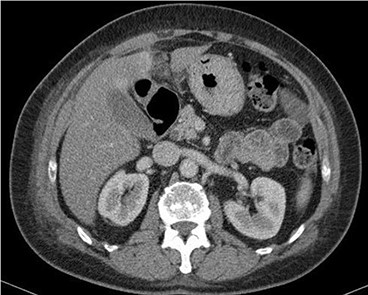

A 53-year-old fit and well woman presented to the emergency department with acute epigastric and right hypochondrium pain with a positive Murphy’s sign of the abdomen. The patient was anicteric and apyrexial. Blood tests performed revealed a white cell count of 13.6 × 109/L and a C-reactive protein of 110 U/L. Liver function tests, amylase and urea and electrolytes were unremarkable. A working diagnosis of acute cholecystitis was made and the patient commenced on intravenous fluids and intravenous antibiotics. Abdominal ultrasound was performed, which demonstrated no gallstones nor choledocholithiasis and was essentially normal. Given the raised inflammatory markers and persistent abdominal pain, CT scan was performed (Fig. 1). This revealed a 32 × 22-mm oval-shaped fat density lesion with peripheral hyper attenuation adjacent to the falciform ligament, representing intraperitoneal focal fat infarction of the fatty appendage of falciform ligament. Sagittal reconstruction showed a central hyperdense thrombosed vessel secondary to torsion of the falciform ligament (Fig. 2).

Sagittal reconstruction redemonstrates central hyperdense thrombosed vessel secondary to torsion